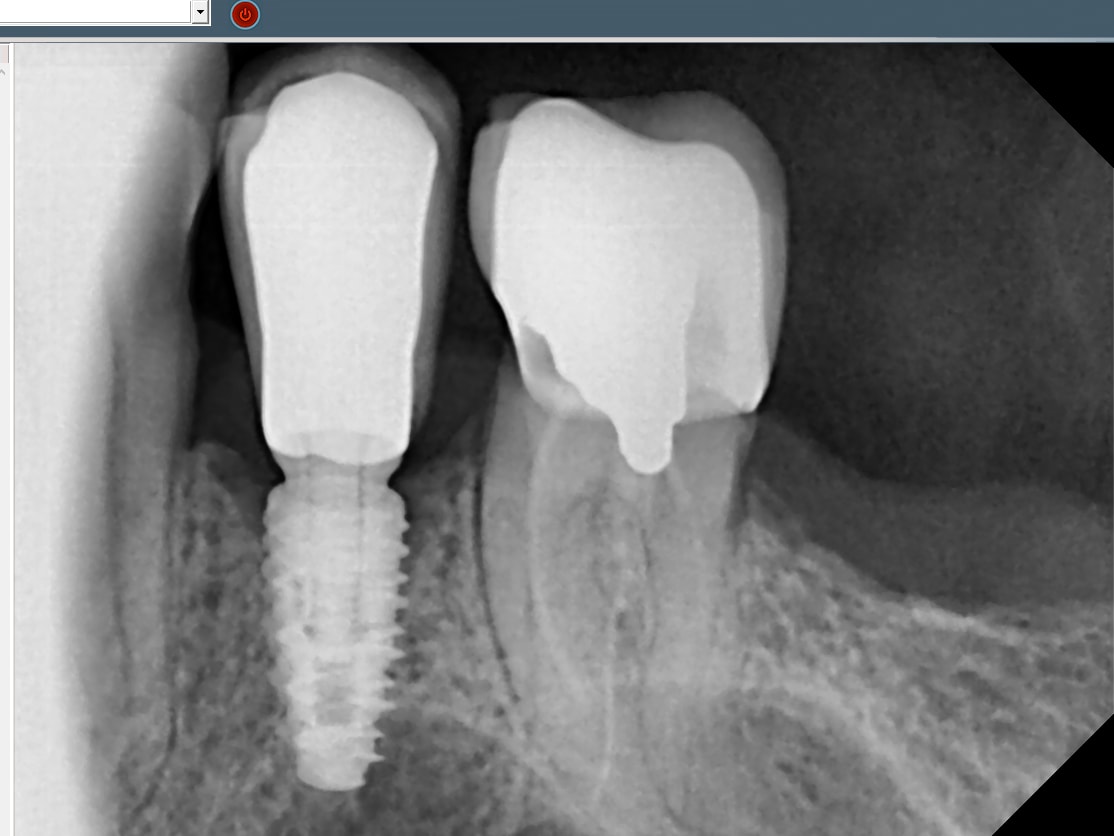

dans ton elan de bonté pluton

le patient vient de m'appeler pour me dire que cette couronne sur l'implant est tombée

c'est quoi comme implant?

de plus visiblement d'apres lui le puit de couverture dans la couronne est toujours en place ,il doit m'envoyer une photo

ce qui supposerai

1/vis fracturée

2/le puit de couverture de la vis n'etait comblé a fond

04/05/2022 à 17h57

Kontact Biotech

https://www.spotimplant.com/fr/implants-dentaire/biotech-dental/kontact